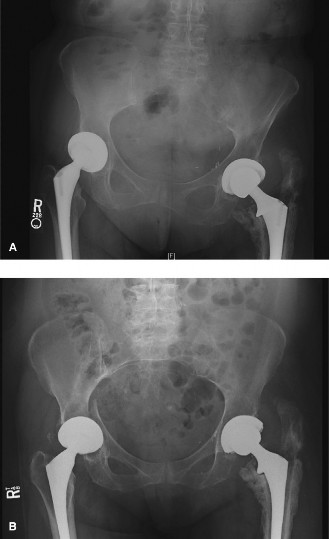

A 64-year-old patient with rheumatoid arthritis and seizure disorder presents to you for evaluation of a pain…